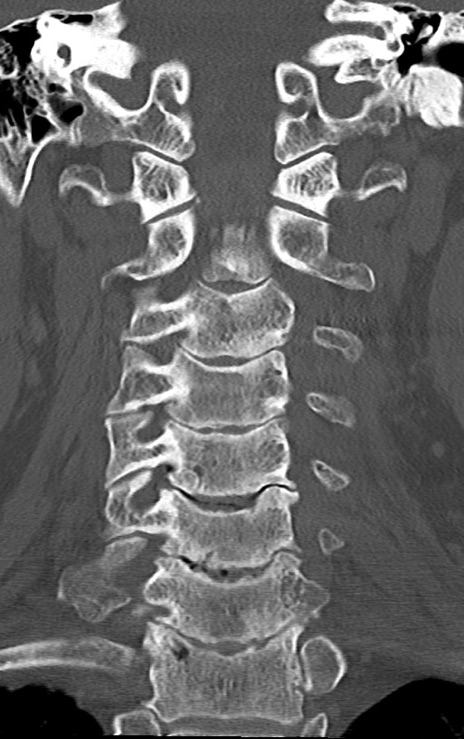

頚椎CT

矢状断像